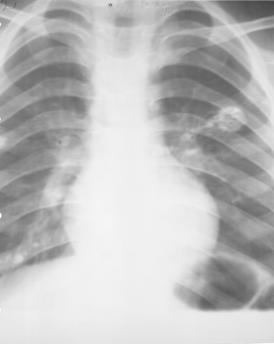

pleureziile mari opacifiaza intreg hemitoracele, la fel ca si revarsatele medii daca examenul este facut in decubit; se constata in plus deplasarea organelor mediastinale si coborarea hemidiafragmului